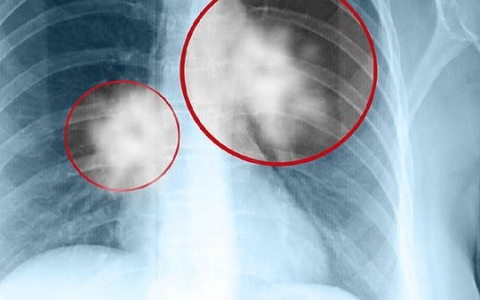

肺淋巴结肿大吃什么药好得快

肺淋巴结肿大的治疗需要根据具体情况选择合适的药物。通常情况下,异烟肼、利福平、吡嗪酰胺和乙胺丁醇等抗结核药物是常用的选择,而阿莫西林则适用于细菌感染。如果症状持